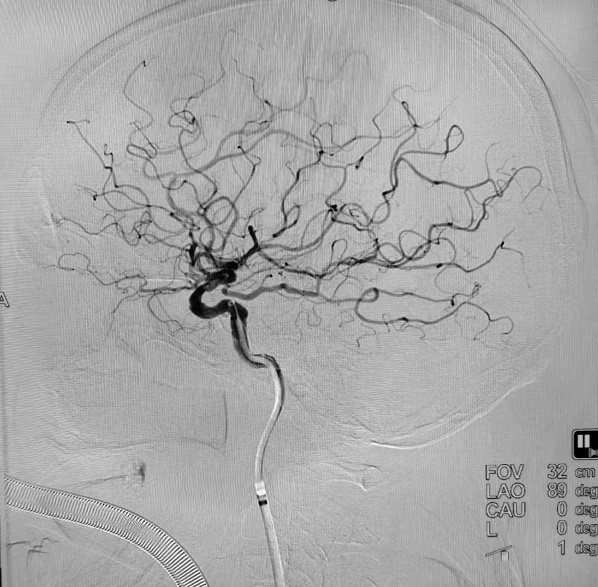

术后DSA

“时间就是大脑”,治疗每延误1分钟,将有190万个脑细胞死亡,等不来、缓不得、也拖不起,轻则导致偏瘫、失语,重则导致死亡。左大爷被送往手术室后,纪文军主任医师带领介入治疗团队立即对他进行了全脑血管造影术检查,术中进一步确诊患者的右侧颈内动脉末端完全闭塞,远端血管不显影。随后,由纪文军主任医师主刀,在李涛副主任医师和郭谢凡住院医师配合下,应用国内先进的抽吸+支架结合取栓,用快的速度使闭塞的右侧颈内动脉实现了再通,再次造影显示右侧颈内动脉血供恢复通畅,达到血流三级再通。手术过程非常顺利。